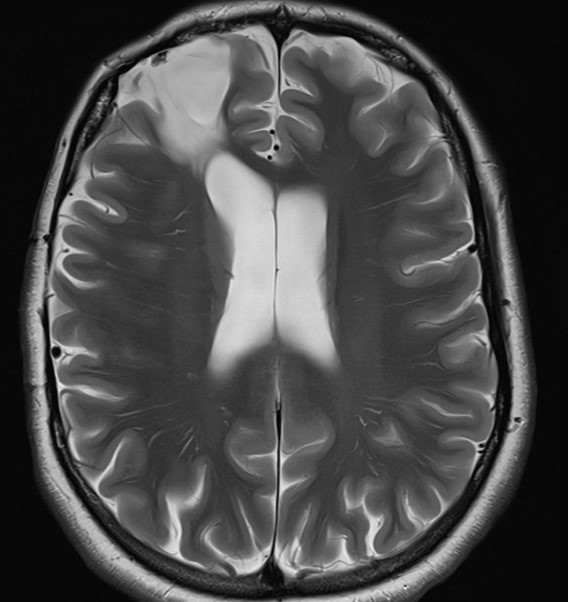

Feb 24, 2026Intellectually normal, traumatic brain injury at the age of 4 months, EEG is normal while awake. The MRI scan is reported to show extensive spongiosis and cavitation in the right frontal lobe. A colleague has treated the patient with lamotrigine for epilepsy for the past few years. He requested a review of the diagnosis.

3. The history provided by the patient and her boyfriend suggests that she either has left frontal lobe seizures or non-epileptic seizures or both. The MRI scan demonstrates an additional, potentially highly significant lesion in the left frontal lobe that was not mentioned in the report.